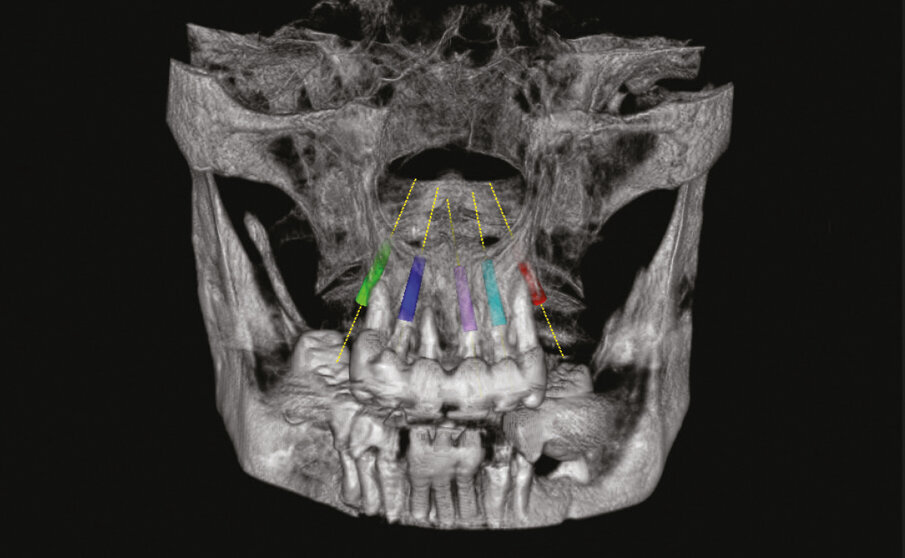

Con il software della CBCT viene progettato il posizionamento di cinque impianti nelle posizioni 15, 13, 21, 22, 25 inclinando i due impianti distali lungo la parete dei seni mascellari (Fig. 2). Questo studio iniziale software-assistito ci sarà di grande aiuto anche se non tradotto in una dima chirurgica per implantologia guidata.

Fig. 2 - Progettazione 3D.